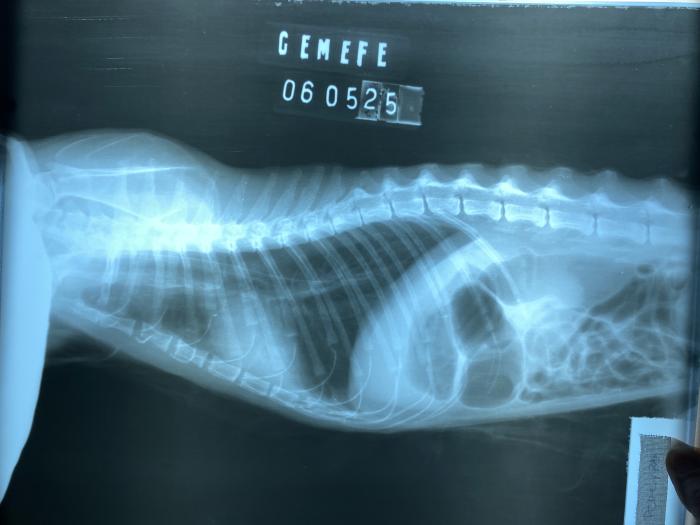

- Radiografía simple de tórax, el primer día de su consulta (Figura 3).

Figura 3. Proyección laterolateral de tórax con sonda nasoesofágica de alimentación hasta el décimo espacio intercostal.